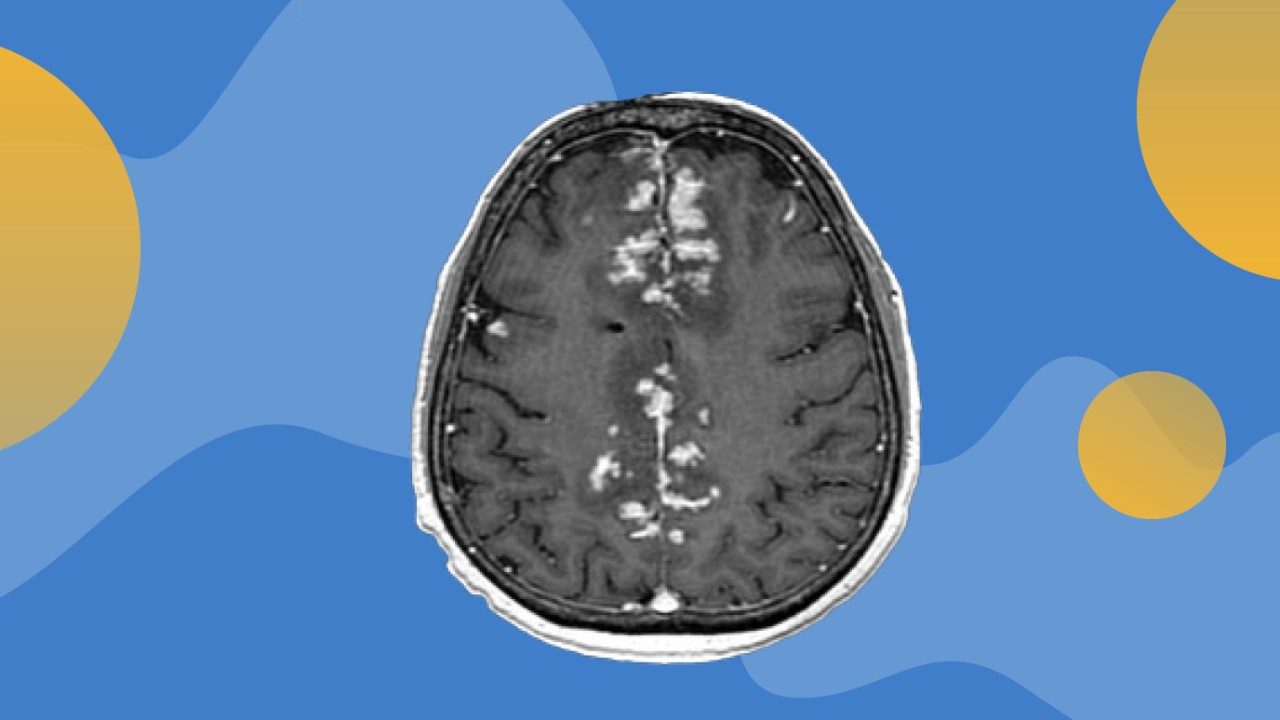

Novel immunotherapy delivery approach safe and beneficial for some melanoma patients with leptomeningeal disease

A novel approach to administer intrathecal (IT) immunotherapy (directly into the spinal fluid) and intravenous (IV) immunotherapy was safe and improved survival in a subset of patients with leptomeningeal disease (LMD) from metastatic melanoma, according to interim analyses of a Phase I/Ib trial led by researchers at The University of Texas MD Anderson Cancer Center.